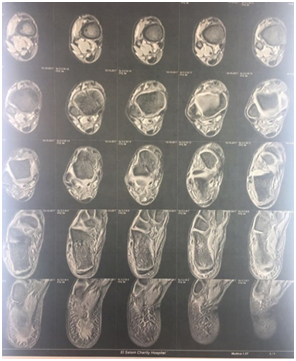

A well-built 14 years old boy presented with severe constant right heel pain which was increased by physical activity, and relieved partially by NSAIDs. He was physically active. The patient denied trauma or fever. He reported no history of other musculoskeletal symptoms. At that time physical examination was apparently normal apart from mild swelling and localized tenderness over the posterior right heel. Laboratory tests were significant for elevated ESR (69 mm) and CRP (12.5 mg/dl). CBC, liver & kidney function tests were normal. RF was negative. X-ray heel findings showed fragmentation &increased density of calcaneal apophysis. Although the patient’s clinical history, the overuse of sports activity, together with the radiographical findings were in line with calcaneal apophysitis (sever’s disease), the unexplained elevation of ESR & CRP made us to proceed to magnetic resonance imaging (MRI)to exclude osteomyelitis. The MRI demonstrated oedema of the calcaneal apophysis with patchy oedema of the calcaneal bone as well as the overlying soft tissue that consistent with Sever disease (Figure 1). Oral anti inflammatory medication was prescribed in addition the patient was advised to use heel raise shoe orthoses and to restrict sports for 6weeks.

Figure 1 legend   MRI demonstrated oedema of the calcaneal apophysis with patchy oedema of the calcaneal bone as well as the overlying soft tissue.